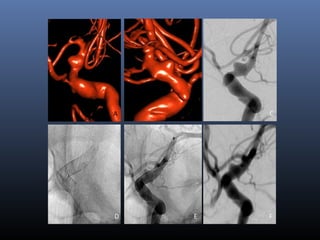

Classical blister aneurysm

34-year M, SAH

Stent …

Further evolution –

flow diverters (stents)

D E F

B CA B